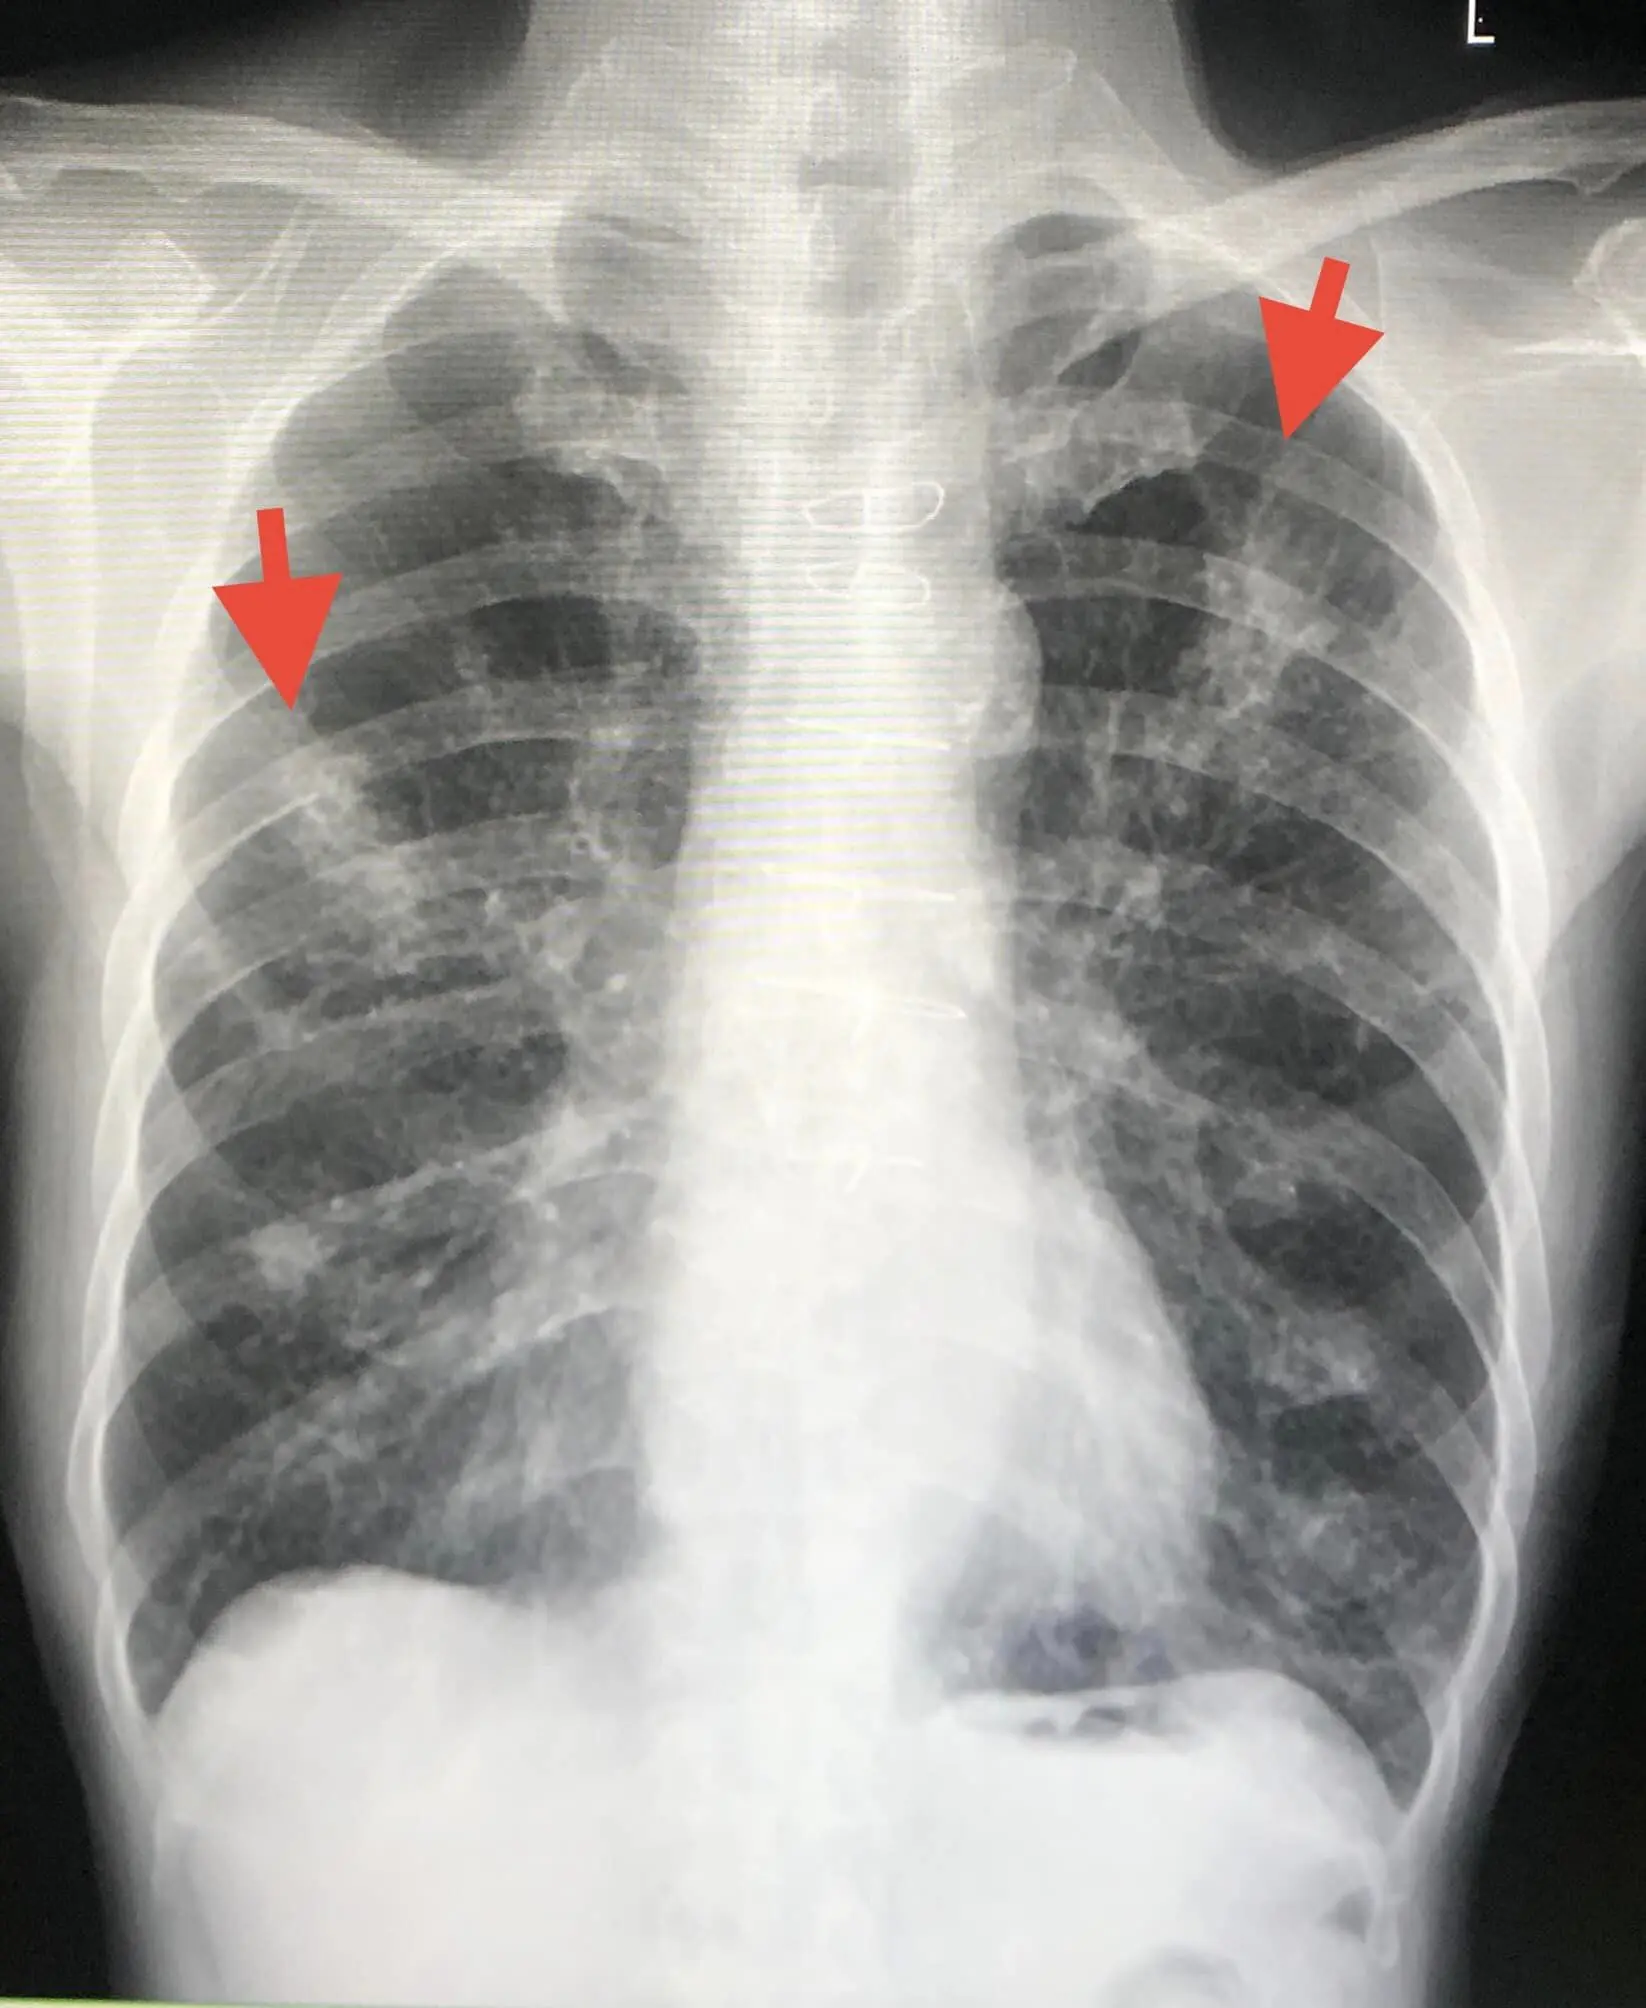

ผู้ป่วยมีอาชีพรับซื้อขายข้าวโพดเลี้ยงสัตว์ และขายปุ๋ยเคมี ตรวจร่างกาย ไม่มีไข้ อุณหภูมิ 37 องศาเซลเซียส ฟังปอดมีเสียงวี๊ด เอกซเรย์ปอด มีปื้นขาวเล็กๆในปอด 2 ข้าง คอมพิวเตอร์สแกนปอดมีฝ้าหลายจุดกระจายในปอด 2 ข้าง

ทำหัตถการส่องกล้องเข้าไปในหลอดลม (Bronchoscopy) พบเสมหะเหลืองข้นเหนียวมากในหลอดลมทั้ง 2 ข้าง ดูดออกมาได้เยอะมาก ส่งน้ำล้างปอด ย้อมไม่พบเชื้อวัณโรค ย้อมพบเชื้อราสาย เพาะเชื้อราขึ้นเชื้อรา Aspergillus fumigatus และ Rhizopus spp. ส่งน้ำล้างปอด bronchial Aspergillus galactomannan antigen ให้ผลบวก

ผลสรุปคือ คนไข้รายนี้ ปอดอักเสบเกิดจากการติดเชื้อรา ได้ให้ยาฆ่าเชื้อราตัวใหม่ Isavuconazole ซึ่งมีราคาแพงมากสามารถครอบคลุมฆ่าเชื้อราได้ทั้ง 2 ชนิด หลังกินยาผู้ป่วยดีขึ้นช้าๆ ไอน้อยลง เหนื่อยน้อยลงผู้ป่วยมีภูมิคุ้มกันต่ำจากการกินยาเสตียรอยด์ต่อเนื่องเป็นปี

บ้านของผู้ป่วยติดกับโกดังเก็บข้าวโพดเลี้ยงสัตว์ ผู้ป่วยหายใจสปอร์ของเชื้อราที่เจริญงอกในเมล็ดข้าวโพดเข้าไปในปอด ต้องให้ยาฆ่าเชื้อราตัวใหม่ต่อเนื่องนานหลายเดือน จนกว่าเอกซเรย์ปอดกลับมาเป็นปกติ